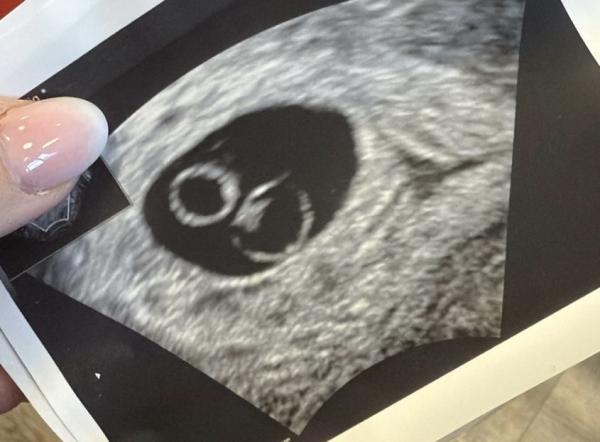

Hallo ihr Lieben, eine Frage, bei mir ist leider alles durcheinander, meine letzte Regel war am 3.11.25, der Eisprung / GV jedoch am 20.11., und ich hatte im September eine OP, daher ist alles sowieso durcheinander gewesen. Die Tests sind alle positiv, HCG steigt, jetzt war am 22.12. die Fruchthöhle zu sehen, heute beim Ultraschall scheint es gewachsen zu sein, aber kein Herzschlag, die Ärztin denkt eher so 6+1, durch das Durcheinander. Ich soll am Freitag wiederkommen. allerdings war der letzte Ultraschall gerade mit zwei dottersäcken, sie sagte aber, der eine sei eine Anlage, der andere nicht. Habt ihr sowas schon mal gehabt? viele grüße und vielen Dank!